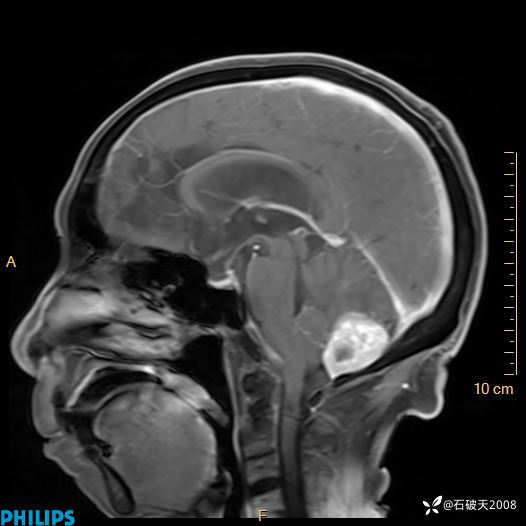

书上说这个肿瘤发生在幕下仅4.09%,你会想到它吗?(病理已公布)

女 86岁 主 诉:乏力1月

现病史:患者1月前活动出现双下肢乏力,无头晕、头痛、恶心、呕吐、肢体活动不利,休息后缓解,间断断发作,症状进行性加重,在家口服药物治疗(具体不详),效差,为进一步诊治,来我院,门诊按“乏力”收住我科,患者自发病以来,神志清,精神稍差,饮食睡眠欠佳,大小便正常,体重未见明显改变。

T2

增强矢状位